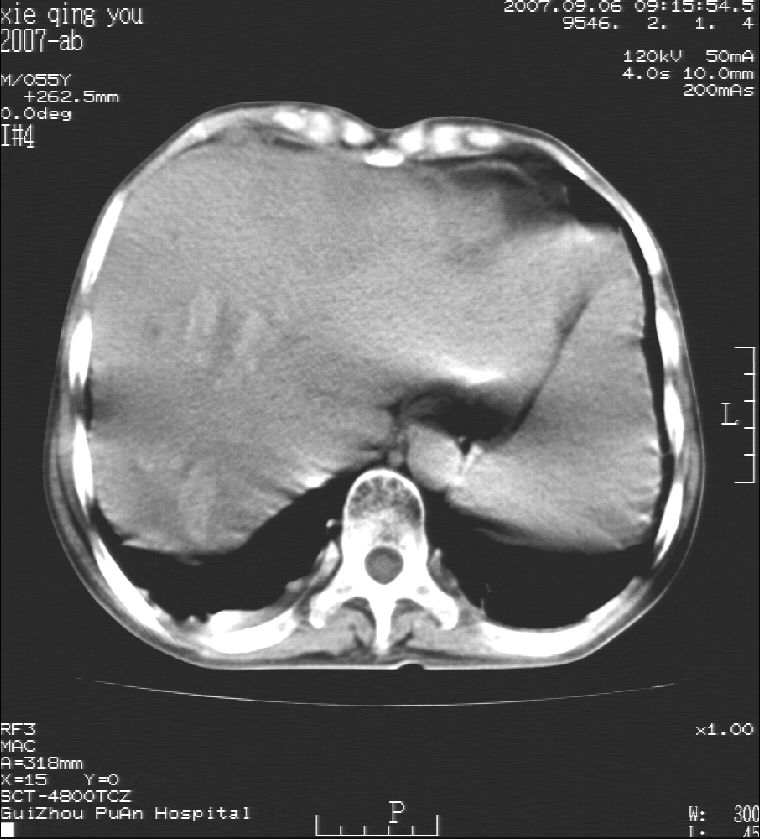

2007年9月片

因是普通ct不能做增强

这个病灶很有意思,怎么可能没有了呢?我考虑当时很可能是肝脏脓肿(b超示囊肿是有可能误诊的,因为影像表现都是低回声吗?),现在脓肿吸收了,肝脏萎缩,肝裂增宽了.别的肝叶代偿增大,不过现在左内叶的确有个占位,肝内多发结石,脾脏比以前大,不排除有肝硬化可能.建议增强扫描给于定性!!!!

肝硬化\\脾大,肝左叶肝癌可能性大,建议增强扫描.肝内胆管多发性结石.

肝硬化、脾大、肝内胆管多发结石。肝左叶低密度占位。建议增强扫描.排除肝癌

肝内胆管多发性结石;肝硬化脾肿大;肝左叶肝癌可能性大,建议增强。